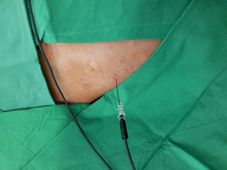

圖、高頻熱凝療法治療五十肩

所謂五十肩或是冰凍肩,主要是肩部肌腱發炎、受傷造成,治療除了休息以外最重要是復健牽引治療,高頻熱凝療法可以有效減緩疼痛,減少止痛藥使用頻率,增加復健成效。